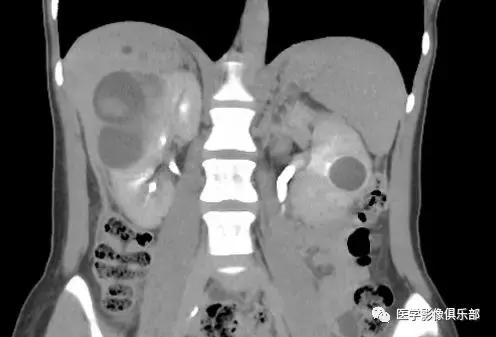

[病例举例]:25岁女性,双肾多发囊肿。

双侧肾脏皮质内数枚类圆形囊肿。